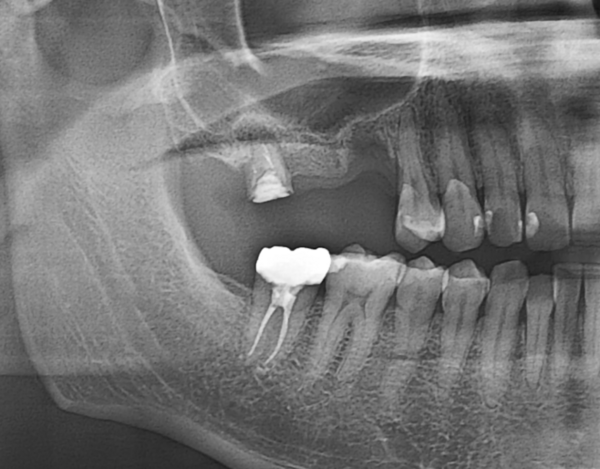

患者様は20代の女性。右下5番目の歯の中心結節という歯の一部が破折してしまったことで痛みを感じて来院された症例です。

痛みの原因は、歯髄腔(神経の部屋)まで到達した破折から感染を起こしてしまったためでした。このためレントゲンでみると歯の根先部には、小指大の大きさの黒い透過像があり、ここに炎症の際に出る膿などが溜まり根尖病変が確認されました。

当院でマイクロスコープ(歯科用顕微鏡)を用いて感染根管治療を行い、根っこの先までお薬で緊密に封鎖しました。

治療後、痛みも治まり噛んでも問題なかったので、この症例ではご自身の歯が多く残せる治療法の、コンポジットレジンの直接法(CRを用いたダイレクトボンディング)で完了しました。